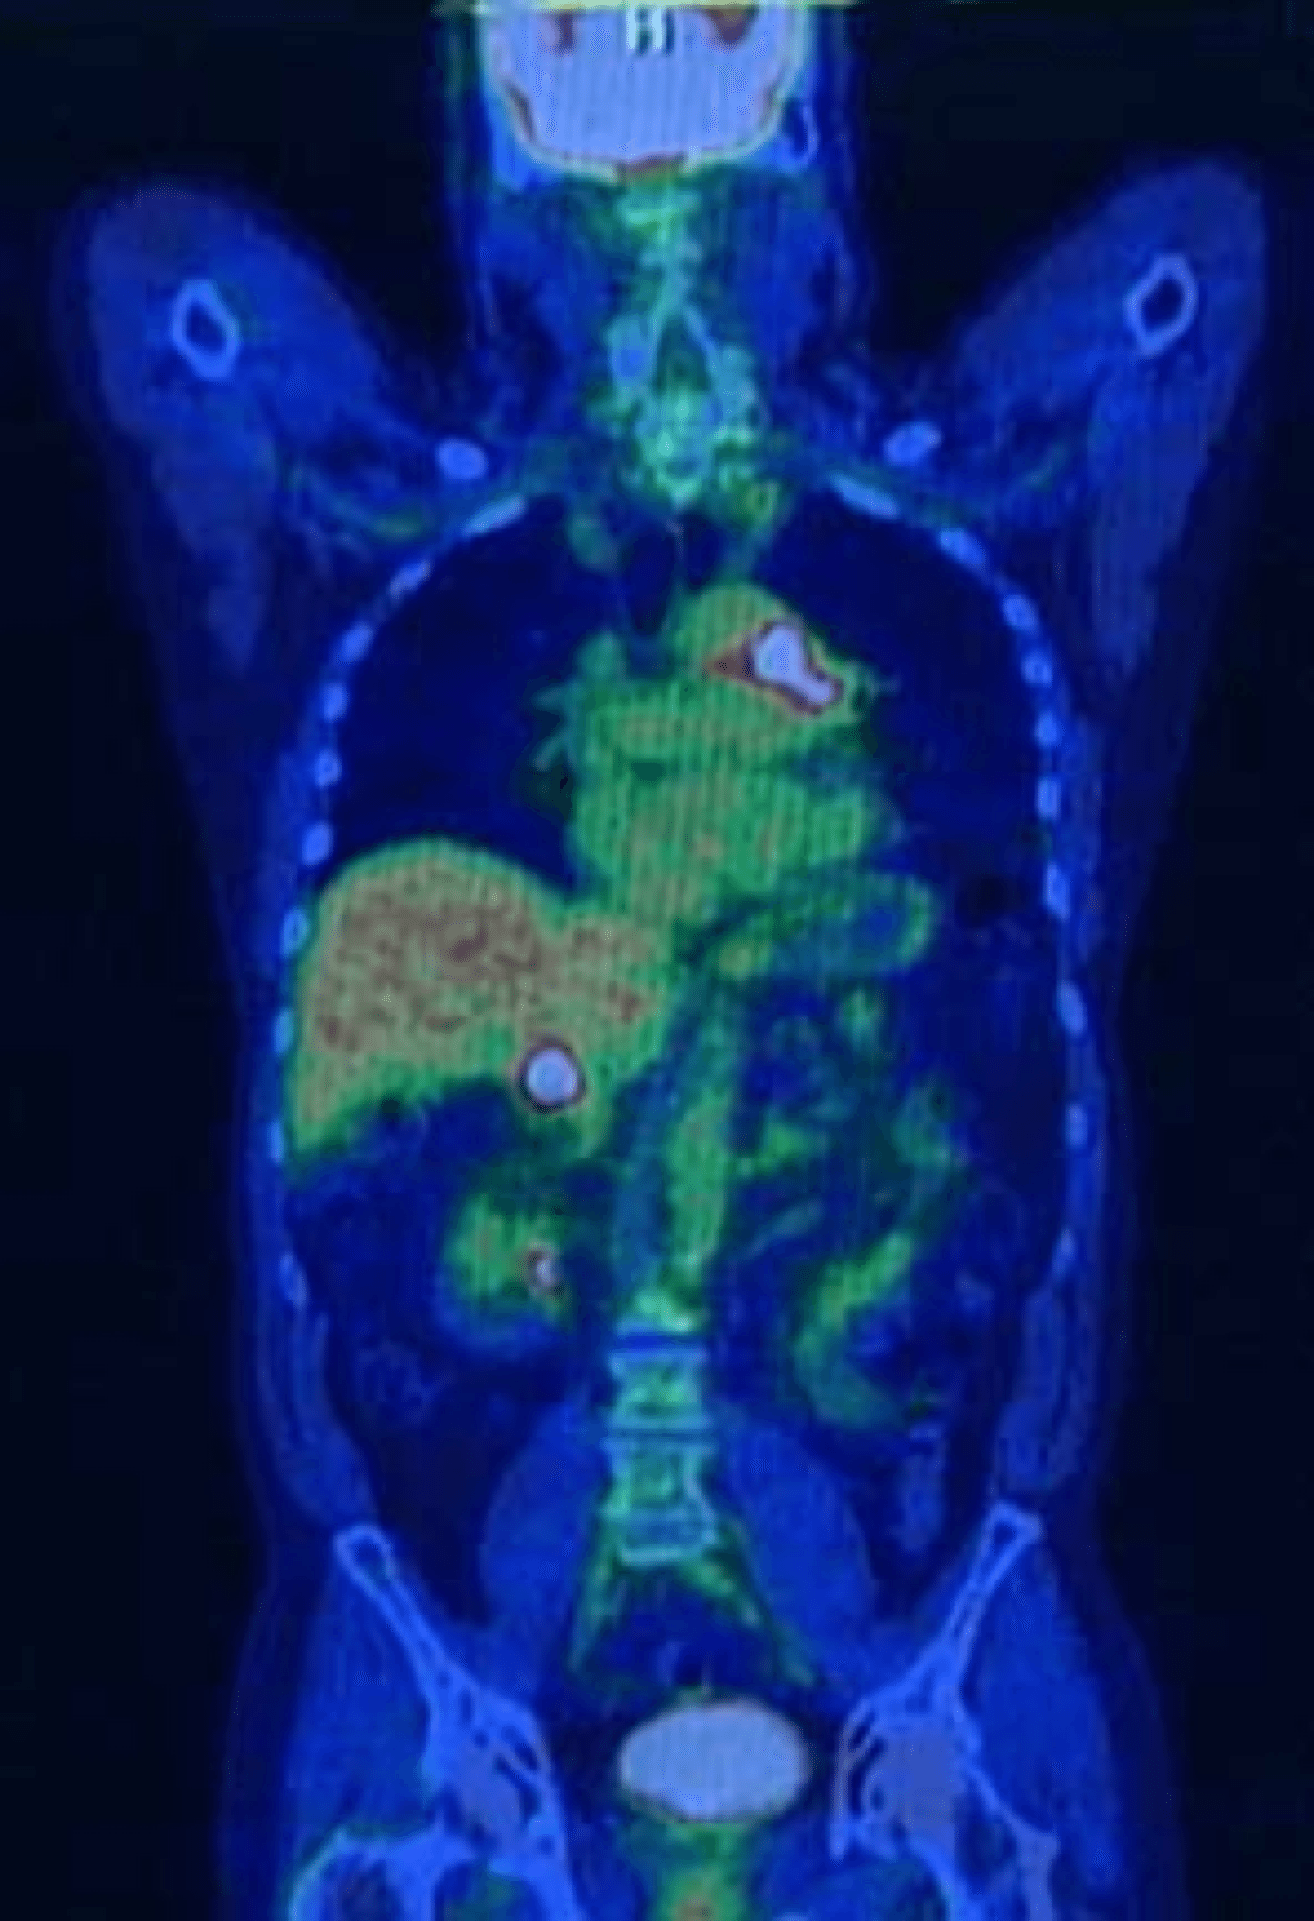

What Is Pet In Medical Imaging . A positron emission tomography (pet) scan is a medical imaging technique that allows doctors to observe metabolic processes and chemical activity in the body. A positron emission tomography (pet) scan is an imaging test that allows your doctor to check for diseases in your body. Pet is a type of nuclear medicine procedure that measures metabolic activity of the cells of body tissues. Used mostly in patients with brain or. Positron emission tomography (pet) uses small amounts of radioactive materials called radiotracers or radiopharmaceuticals, a special camera and a computer to. A positron emission testing (pet) scan is a painless medical imaging test that uses a radioactive tracer (compound) to generate images of the body.

Used mostly in patients with brain or. Pet is a type of nuclear medicine procedure that measures metabolic activity of the cells of body tissues. Positron emission tomography (pet) uses small amounts of radioactive materials called radiotracers or radiopharmaceuticals, a special camera and a computer to. A positron emission tomography (pet) scan is an imaging test that allows your doctor to check for diseases in your body. A positron emission testing (pet) scan is a painless medical imaging test that uses a radioactive tracer (compound) to generate images of the body. A positron emission tomography (pet) scan is a medical imaging technique that allows doctors to observe metabolic processes and chemical activity in the body.